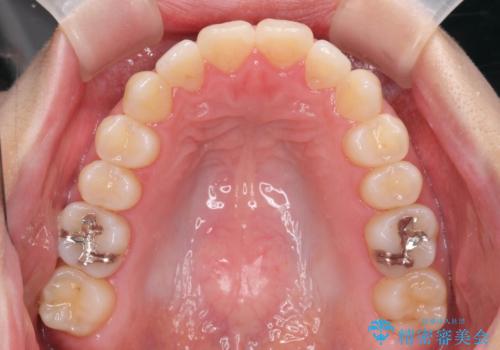

矯正治療後、前歯のがたつき、咬合関係が改善され満足いただくことができました。